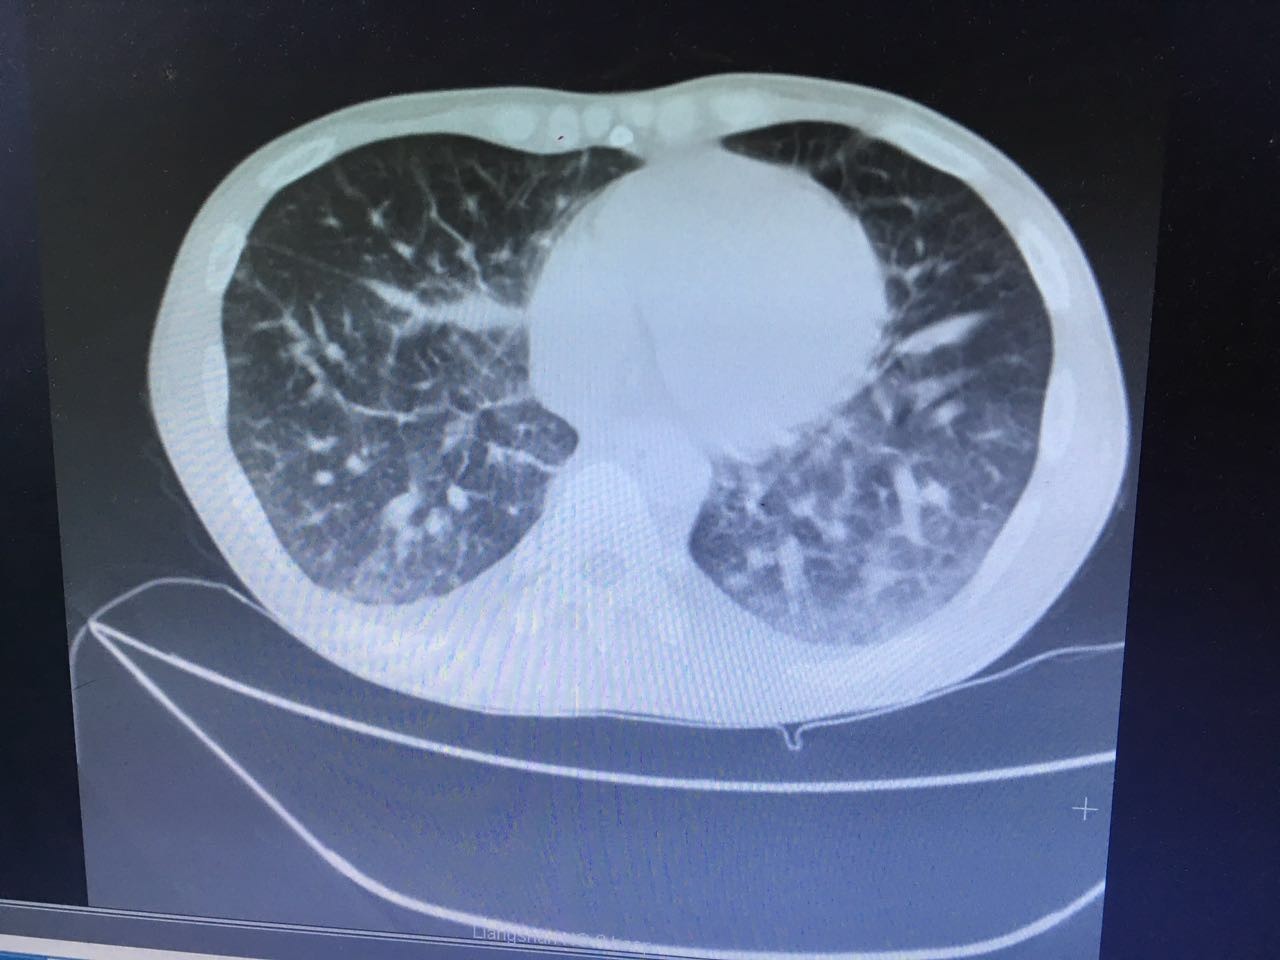

第二天,肺部CT做下来,我们傻了,和胸片差别太大了!从中下肺开始,那是大片的阴影啊!CT提示为间质性肺炎,找放射科主任读片,认为不符合肺结核、肺癌的表现(图1-3.)马上再回到病床前再次确认——没有吸烟史、没有慢性咳嗽史、没有咯血、没有盗汗史。再查体:浅表淋巴结确实不肿大,双肺呼吸音可以算略粗糙也可以算清晰。——这么这么静默的肺部体征,这么这么差的影像学结果,马上补查肿瘤标志物和自身免疫全套吧!

图2